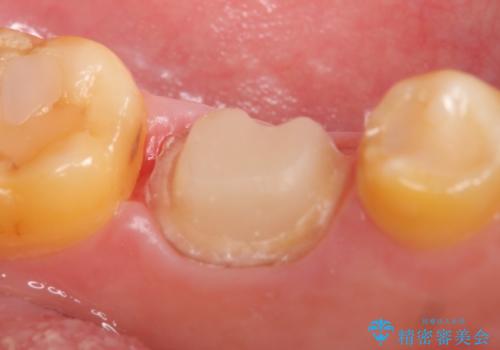

咬合痛等の症状の緩解、根尖病変の縮小傾向、および深かったポケットが正常値まで改善したことを確認後、オールセラミッククラウンによる補綴を行いました。

オールセラミッククラウンの色に関しては、患者様の希望により他歯より白い色で製作しました。

今回用いたオールセラミッククラウンはジルコニアフレームという白い素材の上にセラミックを盛っているため、審美性が非常に高いのが特徴です。

また、ジルコニアは人工ダイヤモンドの材料にも使われているほど高い強度を持っており、そのためオールセラミッククラウンは審美性だけでなく、奥歯やブリッジの補綴も可能とするクラウンです。